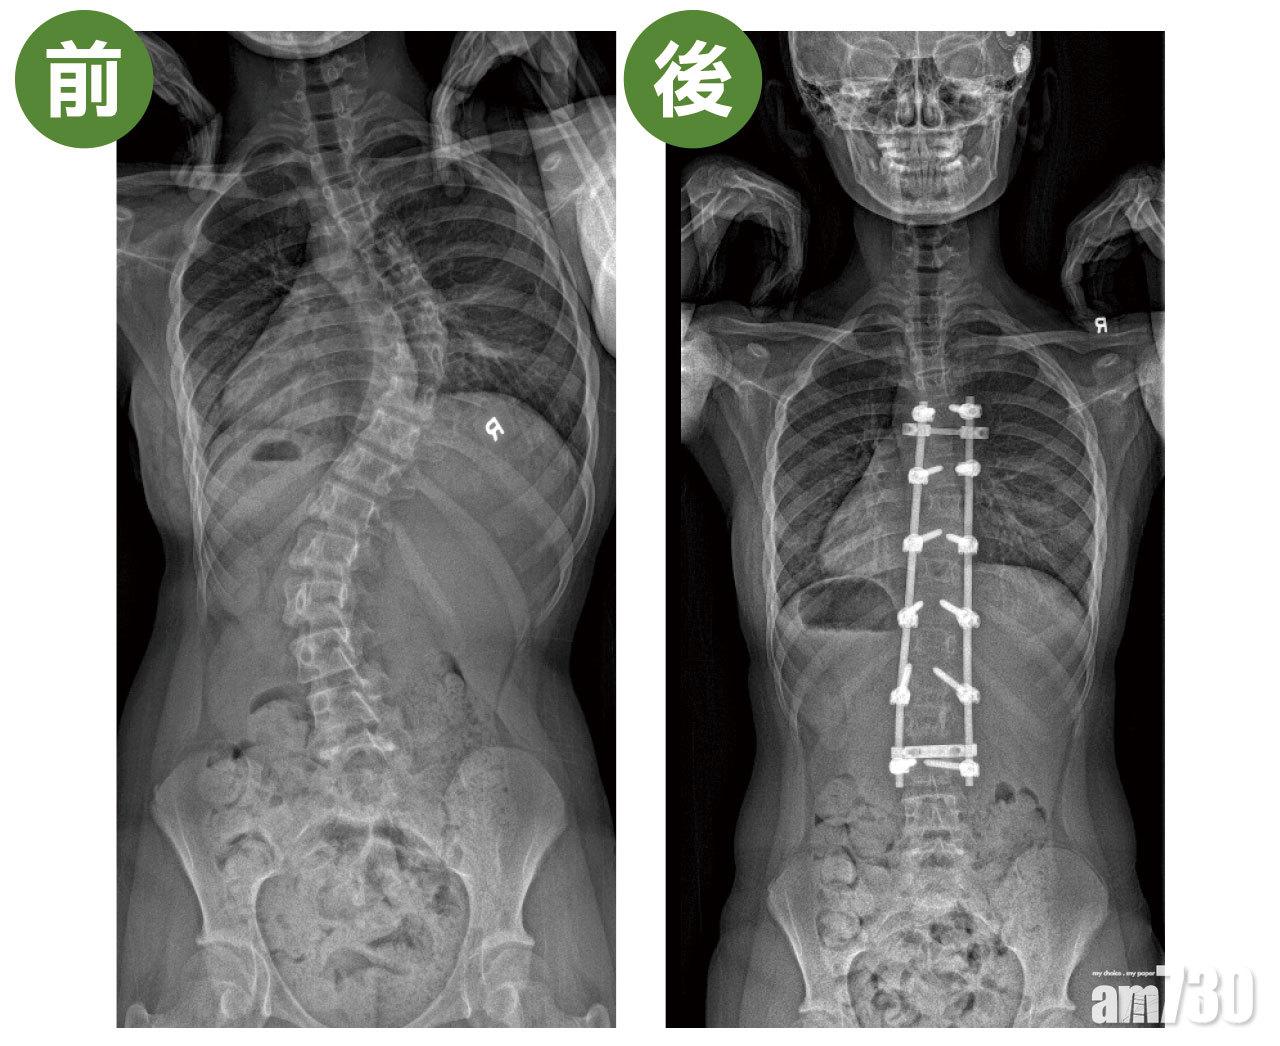

13歲的晴晴(化名)一直不知道自己脊柱有毛病,直到某次游水,媽媽發現她的脊骨向左邊嚴重彎曲,有高低膊和肋骨拱起,於是帶她求診。經臨床診斷及X光檢查,確診是俗稱「C」型的脊柱側彎,弧度達64度(正常是0度)。由於晴晴已來經一年,過了發育階段,骨齡比較大,加上她脊柱側彎嚴重,所以不適合用保守性治療,手術是唯一方法。

晴晴採用開放式手術,於胸椎第2至第12節植入螺絲,拉直脊柱曲線,並進行脊柱融合。手術後3日她已經可以落床,第6日出院。關日康表示,「一般來說,學童休息兩星期便可復課,3個月後可以上體育堂,待半年後脊骨完全融合,就可回復一切正常活動。」

手術前,患者脊柱側彎嚴重,身體開始出現傾側的情況。手術治療透過在胸椎植入螺絲,拉直脊柱曲線。